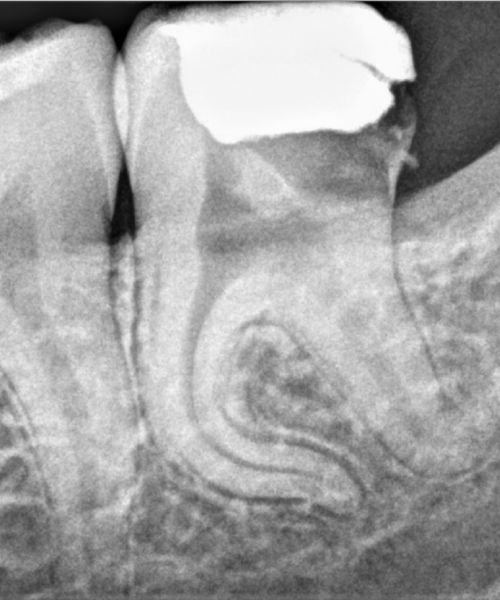

Klīnika piedāvā pacientiem veikt kvalitatīvu mutes dobuma diagnostiku - apskati , kā arī zobu rentgenu. Klīnikā veic augstas izšķirtspējas digitālos zoba rentgenus.